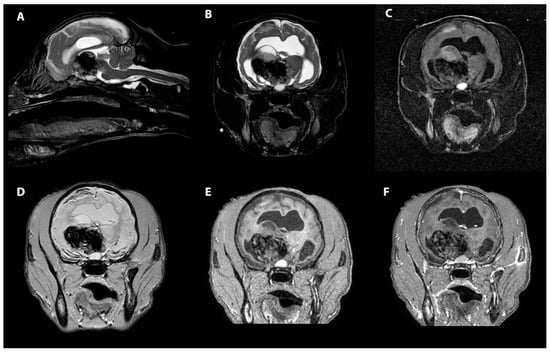

- Young, B.D.; Levine, J.M.; Porter, B.F.; Chen-Allen, A.V.; Rossmeisl, J.H.; Platt, S.R.; Kent, M.; Fosgate, G.T.; Schatzberg, S.J. Magnetic resonance imaging features of intracranial astrocytomas and oligodendrogliomas in dogs. Vet. Radiol. Ultrasound 2011, 52, 132–141. [Google Scholar] [CrossRef]

- Lee, Y.Y.; Van Tassel, P.; Bruner, J.M.; Moser, R.P.; Share, J.C. Juvenile pilocytic astrocytomas: CT and MR characteristics. AJR Am. J. Roentgenol. 1989, 152, 1263–1270. [Google Scholar] [CrossRef] [Green Version]

- Kumar, A.J.; Leeds, N.E.; Kumar, V.A.; Fuller, G.N.; Lang, F.F.; Milas, Z.; Weinberg, J.S.; Ater, J.L.; Sawaya, R. Magnetic resonance imaging features of pilocytic astrocytoma of the brain mimicking high-grade gliomas. J. Comput. Assist. Tomogr. 2010, 34, 601–611. [Google Scholar] [CrossRef]

- Nakano, Y.; Yamamoto, J.; Takahashi, M.; Soejima, Y.; Akiba, D.; Kitagawa, T.; Ueta, K.; Miyaoka, R.; Umemura, T.; Nishizawa, S. Pilocytic astrocytoma presenting with atypical features on magnetic resonance imaging. J. Neuroradiol. 2015, 42, 278–282. [Google Scholar] [CrossRef] [PubMed]